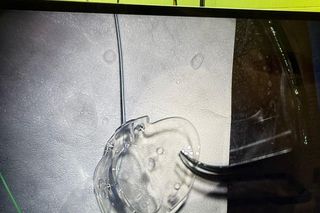

Sam implant przypomina nieco soczewkę. Mierzy ok. centymetra długości i dysponuje kanalikiem. Wszczepia się go do oka, a wspomniany kanalik mocuje w komorze przedniej oka. To on ma za zadanie redukować ciśnienie w gałce ocznej.